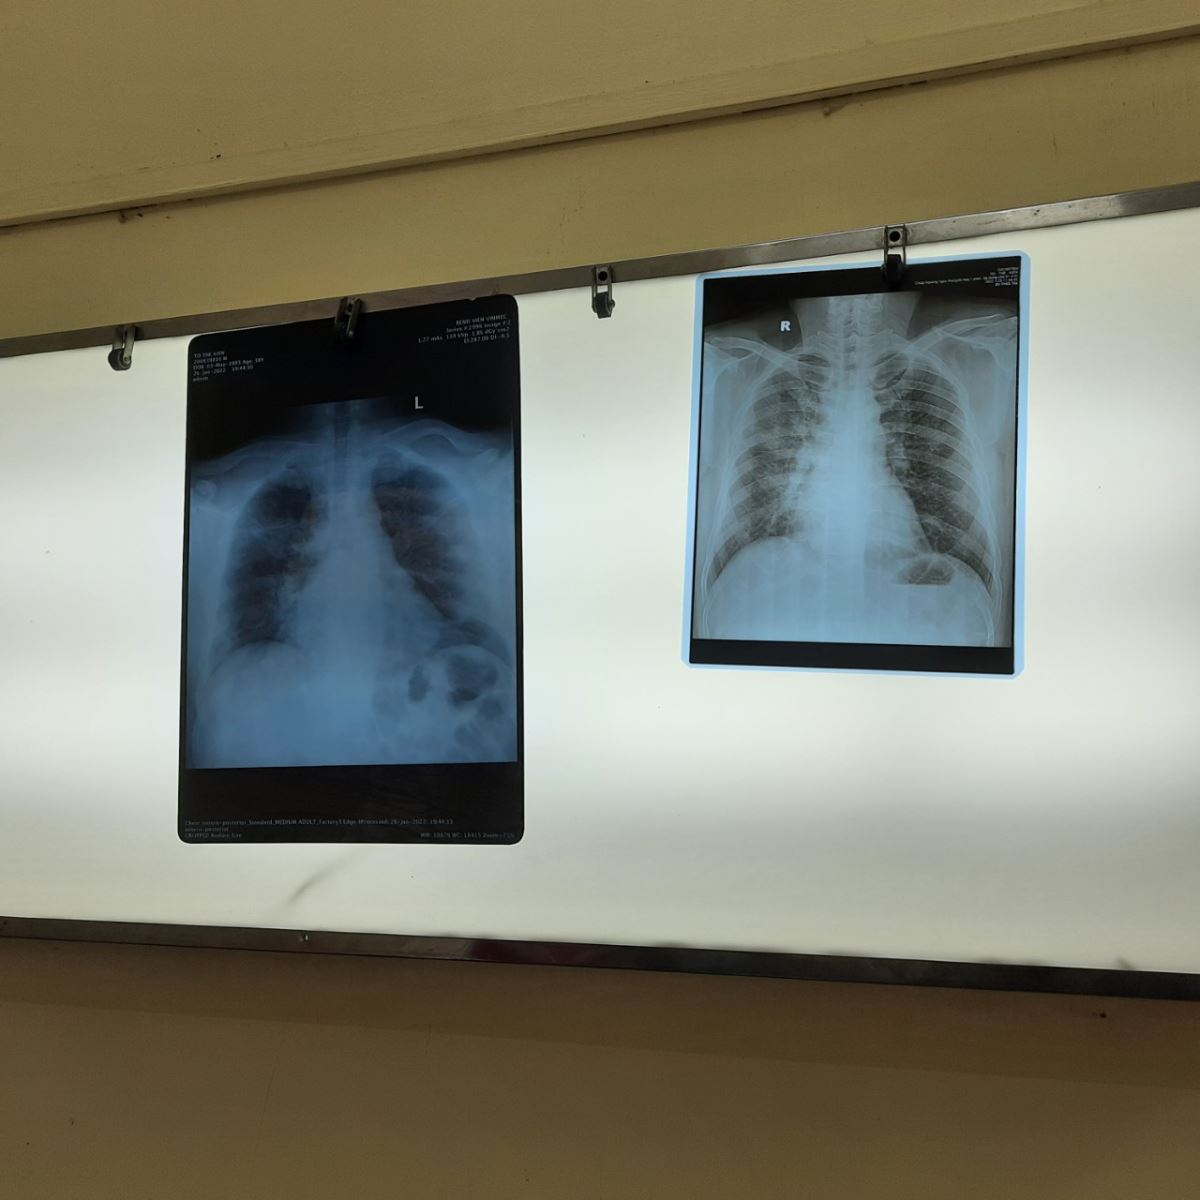

Vì sốt cao liên tục, chỉ số đo SP02 ở nhà tụt xuống 87, 88, hơi thở ngày càng trở lên khó khăn nên đến ngày thứ 8 tôi phải cấp tốc nhập viện gấp để thăm khám. Theo kết quả chụp X-Quang, bác sĩ chẩn đoán, viêm phổi do virus Sars-Cov 2, phổi mờ 2/3, được xếp vào loại khá nặng.

Sau một thời gian điều trị, tôi tiến hành chụp lại X quang phổi, kết quả cho thấy phổi đã có dấu hiệu hồi phục và chỉ còn sốt nhẹ. Ngày 28 Tết test PCR, cho kết quả âm tính nên xin về nhà để điều trị và ăn Tết. Bác sĩ cũng thấy kỳ lạ khi phổi của tôi hồi phục nhanh. Nhưng mặc dù vậy, những hội chứng của hậu Covid vẫn còn tồn đọng nên tôi vẫn tiếp tục xông tinh dầu evytan và tập thở đều đặn mỗi ngày để phục hồi lại chức năng phổi và tinh thần.